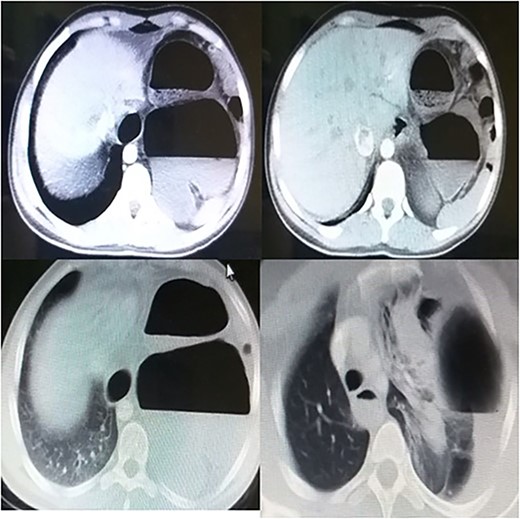

Laboratory tests showed white blood cells count of 9000/microliter with neutrophils 82%, mild anemia (Hb = 10 g/dl) and respiratory alkalosis (pH = 7.46, pCO2 = 28, and HCO3 = 20). Chest x-ray (CXR) of the chest was not able to visualize the left hemidiaphragm with a hollow viscus in the left thoracic cavity and a right shift of the mediastinum (Fig. 1). Computed tomography (CT) scan showed several viscera in the left thoracic cavity, containing air-fluid levels with the fluid not being homogeneous, pushing the left lung, the heart and the mediastinum to the right (Fig. 2). The CT also showed dilation of the esophagus with a presence of a fluid-gas level (Fig. 2). Additionally, there was atelectasis in the left lung. Finally, the liver and pancreas were in their normal position. An endoscopy was performed, which visualized the DH, which was 3 cm.